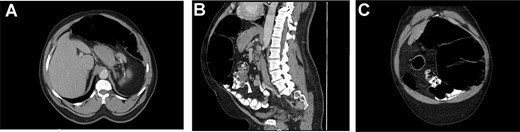

A computed tomography (CT) additionally revealed moderate distention of the transverse segment of colon (Fig. 1A), abnormal appearance of the left upper quadrant mesentery with whorled appearance of the splenic flexure (Fig. 1B), suggestive of partial obstruction and dilation of the colon at the level of the splenic flexure (Fig. 1C). The patient was admitted to the surgical floor for further management.

(A) showing distended transverse colon. (B) Sagittal displaying distended splenic flexure, concern for SFV. (C) Coronal view showing dilated splenic flexure, concern for SFV.